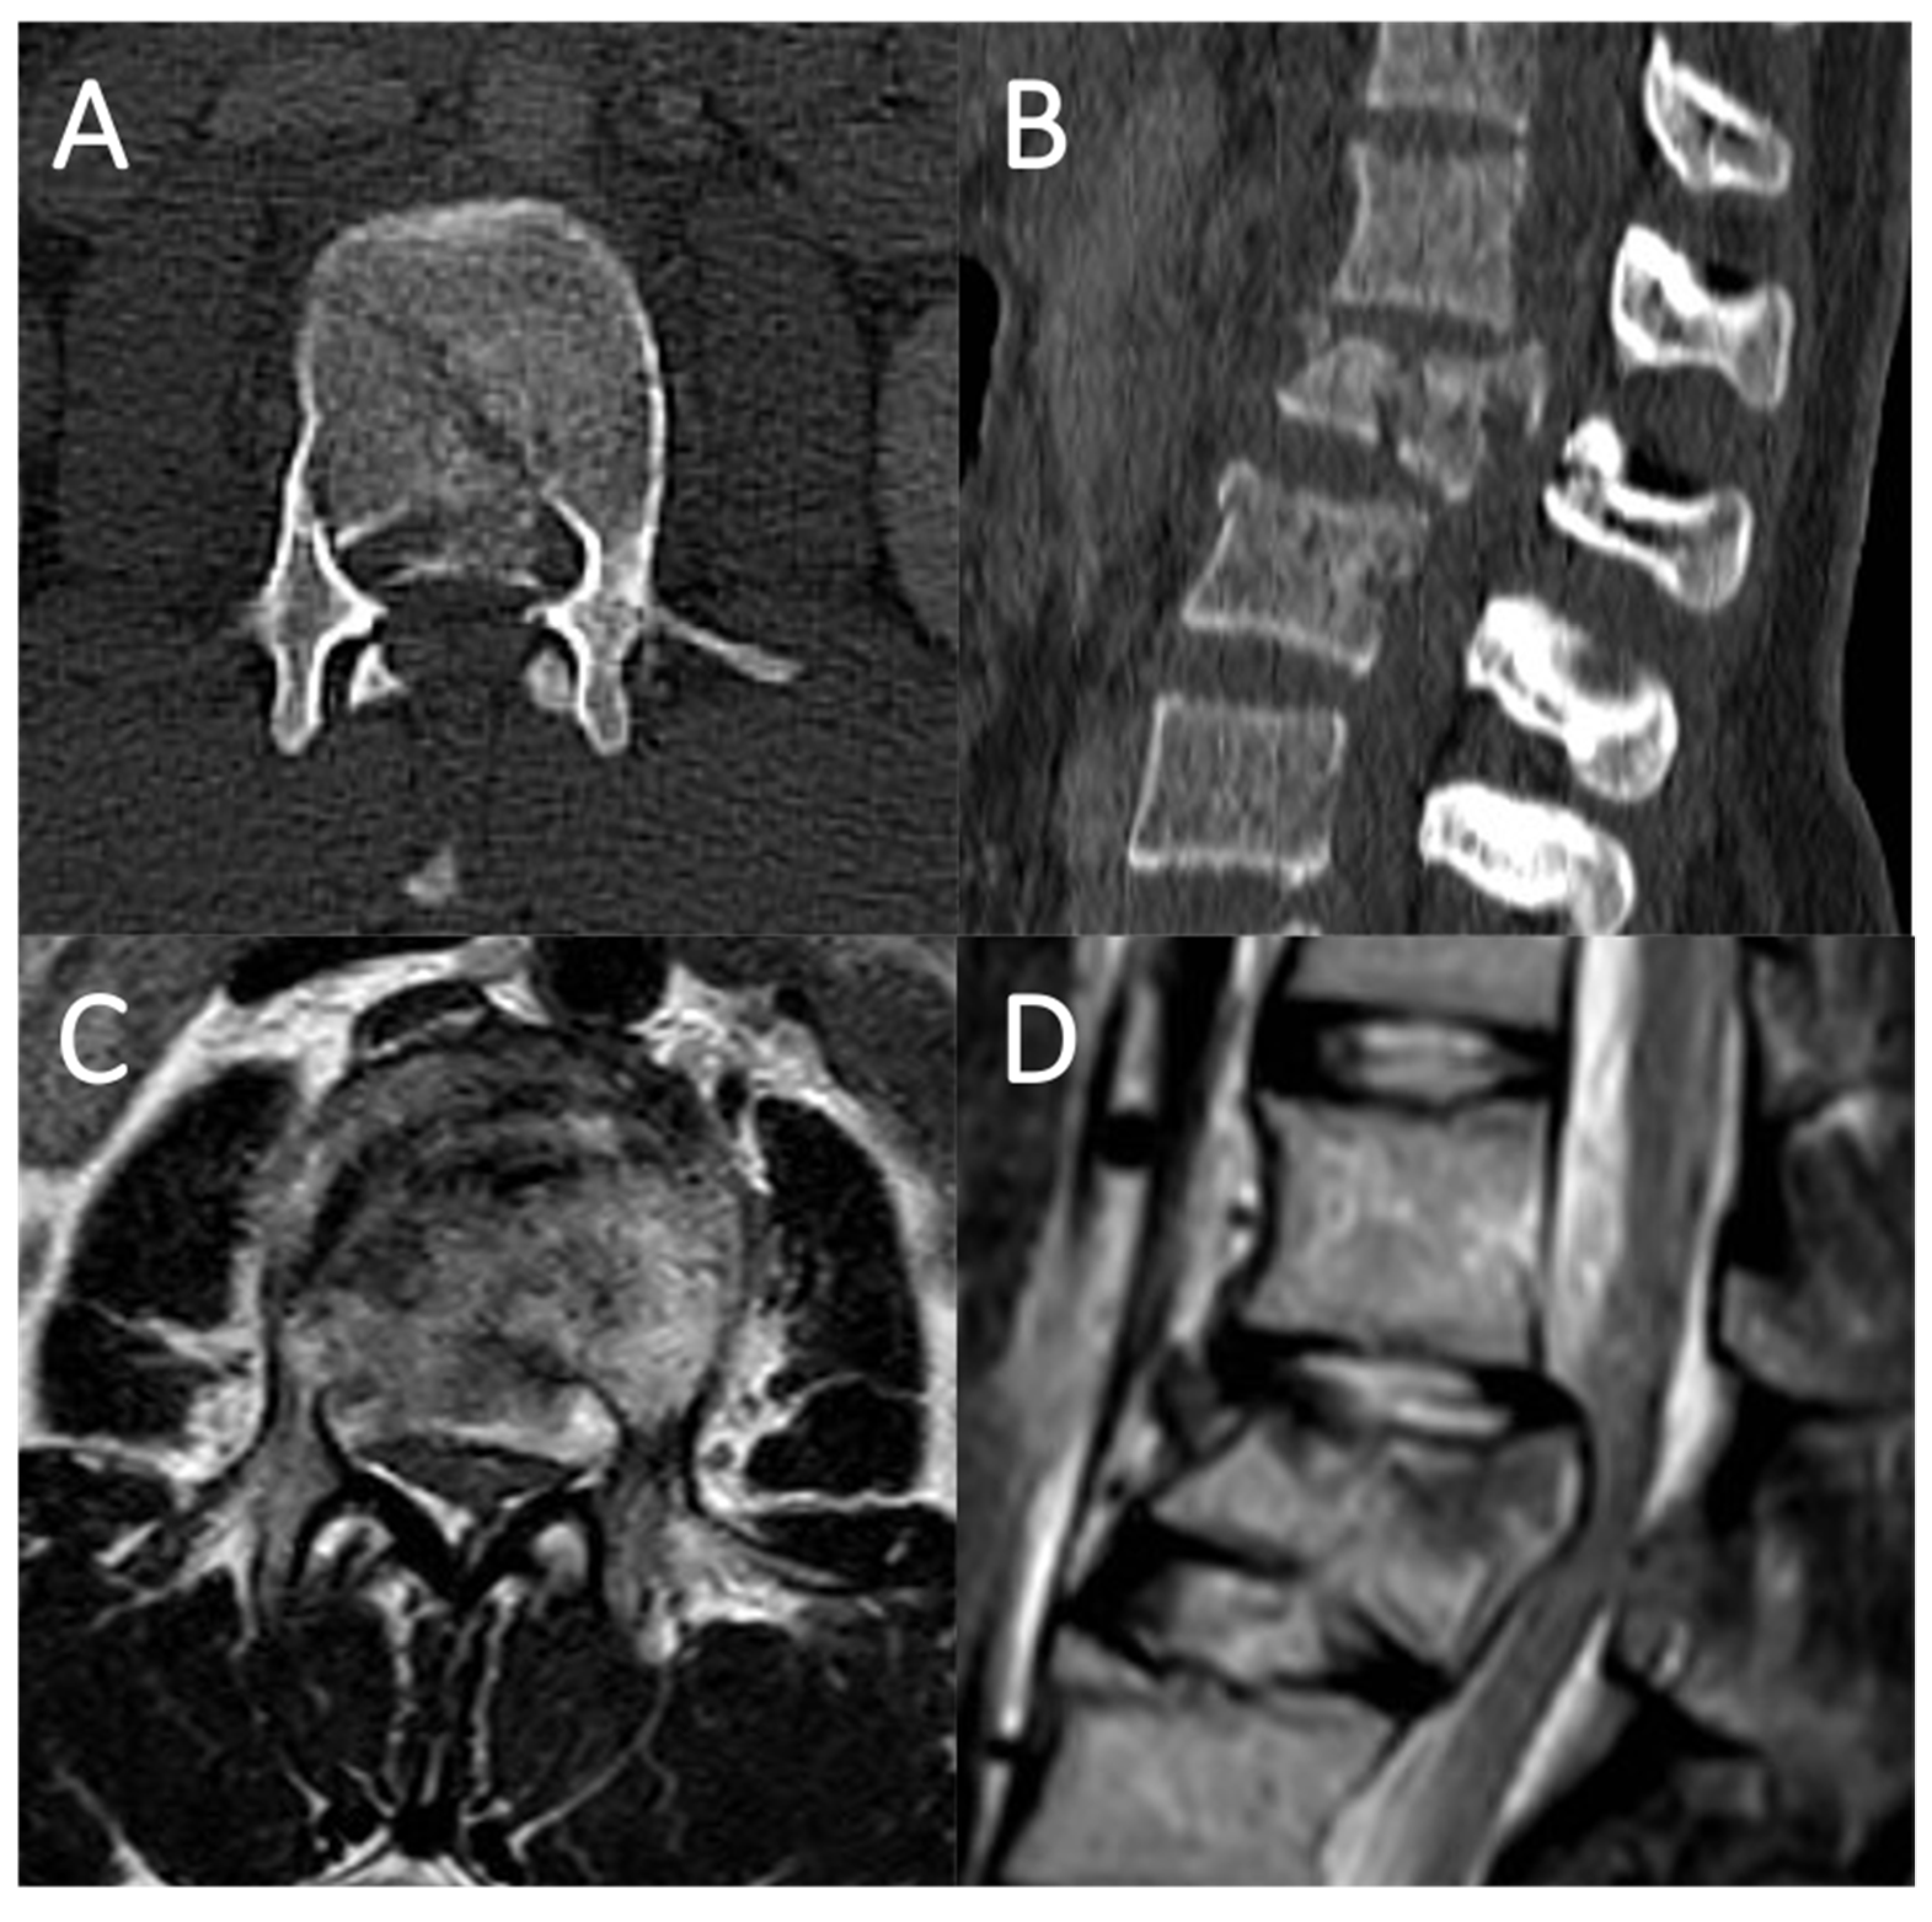

4.1. Case Report 1: Coating

4.2. Case Report 2: Coating Straddling Nerve Roots

4.3. Case Report 3: Coating with Sutured Fat Graft